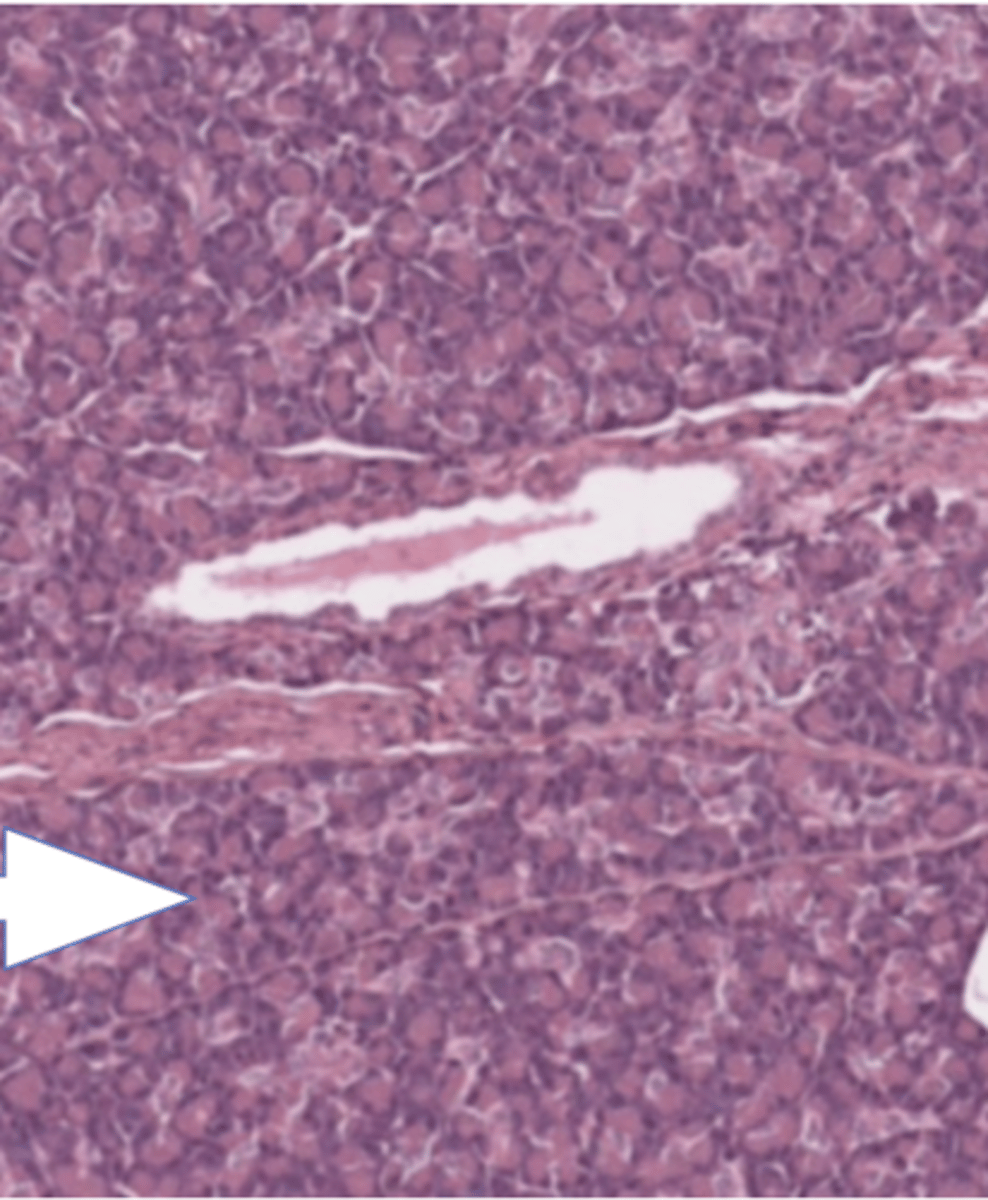

liver lobule

central vein of liver lobule